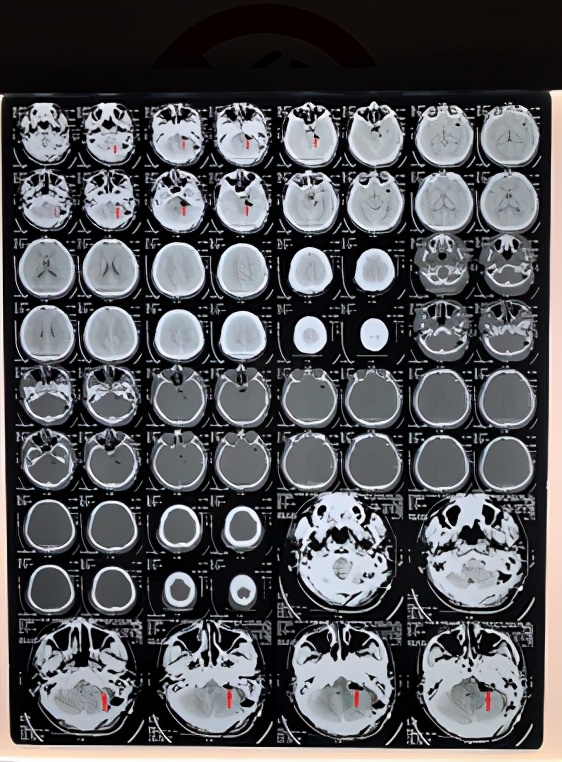

3、术前给予脑血管造影和头颅CT检查了解肿瘤血管分布及乳突情况,选择合适的手术入路。

4、根据上述检查,选择枕下乙状窦后入路肿瘤切除术。